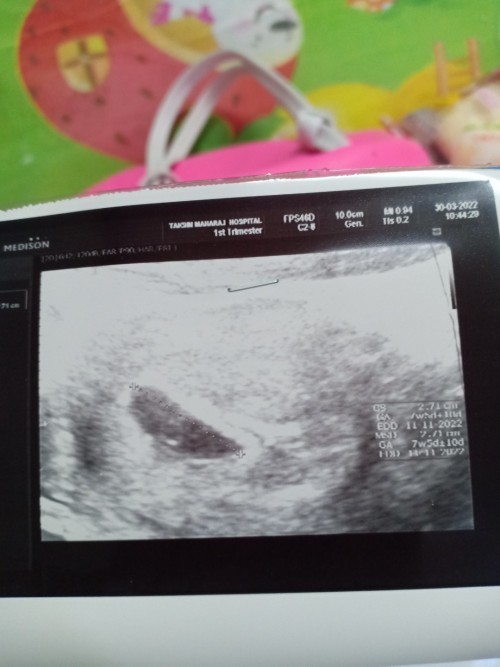

ท้อง9weekไม่พบตัวอ่อน

เราท้องได้9weekแต่ไปซาวกับไม่เจอตัวน้องคะซาวทั้งหน้าท้องและทางช่องคลอดตอนนี้เครียดมากการคัดเต้าก็ยังปกติคะมีเหม็นกลิ่นอาหารบ้างตอนนี้จิตตกเข้าออกตามเว็บหาข้อมูลทำใจไม่ได้เลยคะแม่ท่านไหนเป็นแบบนี้บ้างคะ

7w+3 พึ่งซาวด์มาเหมือนกันคะ ไม่พบตัวน้องเห็นแต่ถุงตั้งครรภ์ที่โตขึ้นกับถุงไข่แดงคะ หมอนัดซาวด์อีกที12w กังวลเหมือนกันคะ กลัวท้องลม แอบเครียด

ของเราไปพบคุณหมอตอน4week เจอแต่ถุงการตั้งครรภ์ ไปอีกครั้งตอน6week เจอหัวใจน้องแล้วค่ะ ตอนนี้9week 5 เห็นตัวน้องแล้ว เป็นกำลังใจให้คุณแม่นะคะ

สรุปเจอมั้ยคะ ตอนนี้เรา 9w 5 d น้องตัวใหญ่ละดิ้นแล้วนะคะ ยังไงแม่อย่าเครียดละลองไปซาวช่องคลอดก่อน ถ้าไม่เจอกะท้องลมคะแม่เราเคยท้องลม

เป็นค่ะ หมอนัดอัลตราซาวด์ซ้ำ เจอแล้วค่ะ ตอนแรกเครียดมากเหมือนกัน แต่ก็พยายามไม่เครียดค่ะ ผลออกมาเจอตัวดิ้นดุ๊กดิ๊กเลย สู้ๆนะคะ

นับจากรอบเดือนครั้งสุดท้ายได้ 9 วีค 5 วันแล้วไปอัลตร้าซาวด์มาเจอแค่ถุงคะ